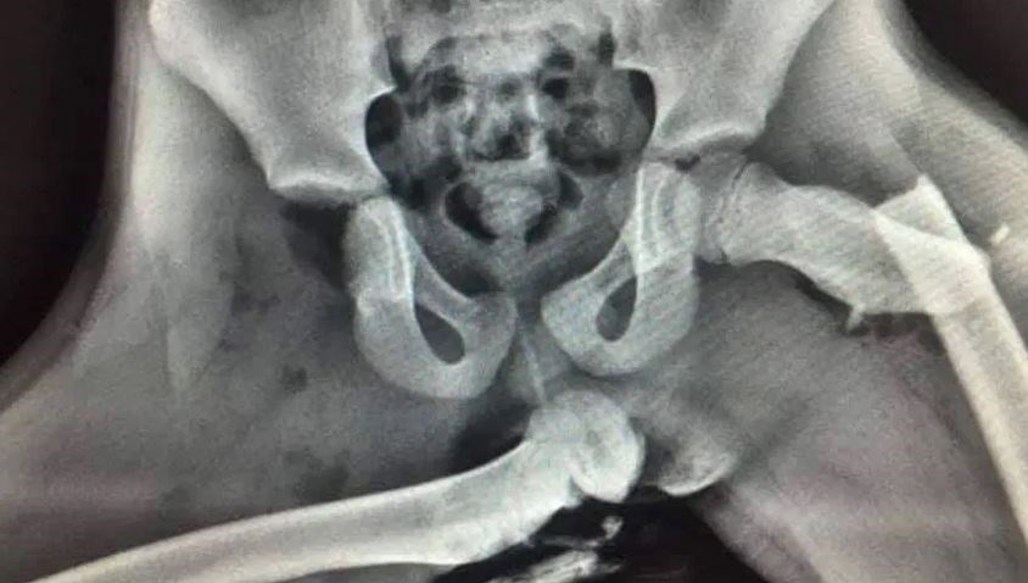

First shared by the West Sussex-based Platinum Ambulance Service on Facebook, the images appear to show the pelvic area. To say that the right femur was dislocated is an understatement, and the left looks to be snapped in two.

Authorities didn't share any information about who the victim in this crash was, but did note that the injuries sustained were "life-changing".

"Here is an X-ray of horrific injuries sustained to the front seat passenger who had their feet on the dashboard at the time of a collision. If you see your passenger doing it stop driving and show them this," Sargent Ian Price said.